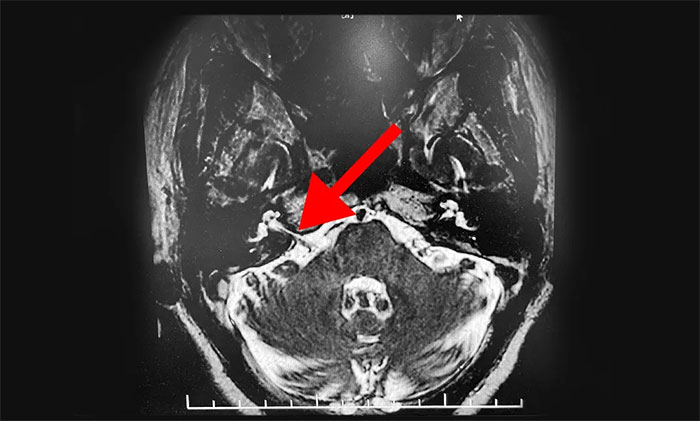

▲患者小脑血管与面神经根关系密切

患者入院查体示,右侧面肌阵发性不自主抽搐,右眼裂变小,口角向右歪斜,神经系统检查无其他异常。

头颅磁共振检查示,患者桥小脑角血管与面神经根关系密切。结合患者病史及相关检查,可明确诊断。